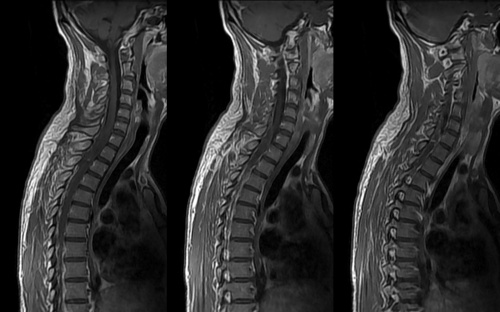

Томография позвоночника

МРТ шейного отдела позвоночника

МРТ пояснично крестцового отдела позвоночника